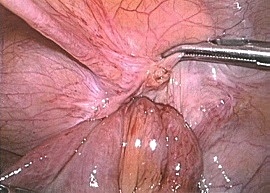

手術画像